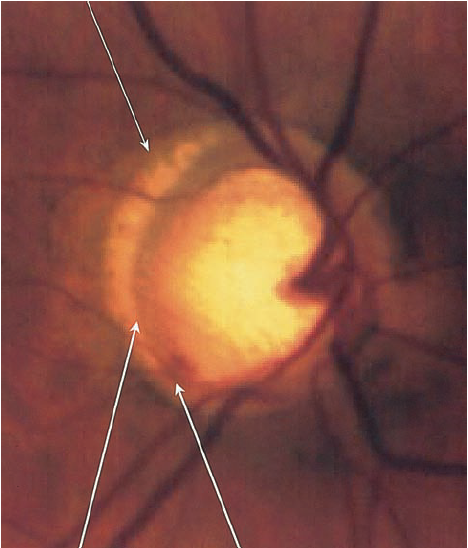

2.2. Gai thị

Tổn hại gai thị không có sự khác biệt với các loại glôcôm khác như tỉ lệ C/D lớn, tổn hại lớp viền thần kinh đĩa thị giác, thay đổi mạch máu của đĩa thị giác…Tuy nhiên, trong glôcôm nhãn áp bình thường tổn hại gai thị cũng có 1 số đặc điểm riêng:

- Lớp viền thần kinh quanh gai thị mỏng hơn so với glôcôm nhãn áp cao.

- Lõm gai không quá sâu và lớp lá sàng ít bị đấy ra phía sau hơn.

- Hay gặp tổn hại viền thần kinh gai thị khu trú ở 1 vị trí kèm theo lõm gai thị sâu và thay đổi lớp lá sàng tạo thành hố gai thị mắc phải, 75% gặp ở glôcôm nhãn áp bình thường so với 15% ở glôcôm nhãn áp cao.

BSVL2

Mất lớp viền thần kinh

Lõm gai sâu

- Một trong những dấu hiệu thường gặp nhất trong glôcôm nhãn áp bình thường  là teo võng mạc cạnh gai thị ( vùng α và vùng β), tuy nhiên dấu hiệu này không đặc hiệu cho glôcôm nhãn áp không cao .

- Xuất huyết gai thị: rất hay gặp trong glôcôm nhãn áp bình thường.

- Tổn hại lớp sợi thần kinh quanh gai thị: hay gặp tổn hại lớp sợi thần kinh khu trú ở 1 vị trí nào đó hơn là tổn hại toàn bộ chu vi gai thị.

Tuy nhiên,  những dấu hiệu trên không đặc hiệu cho glôcôm nhãn áp bình thường , không cho phép chẩn đoán xác định mà chỉ có giá trị gợi ý glôcôm nhãn áp bình thường  mà thôi.